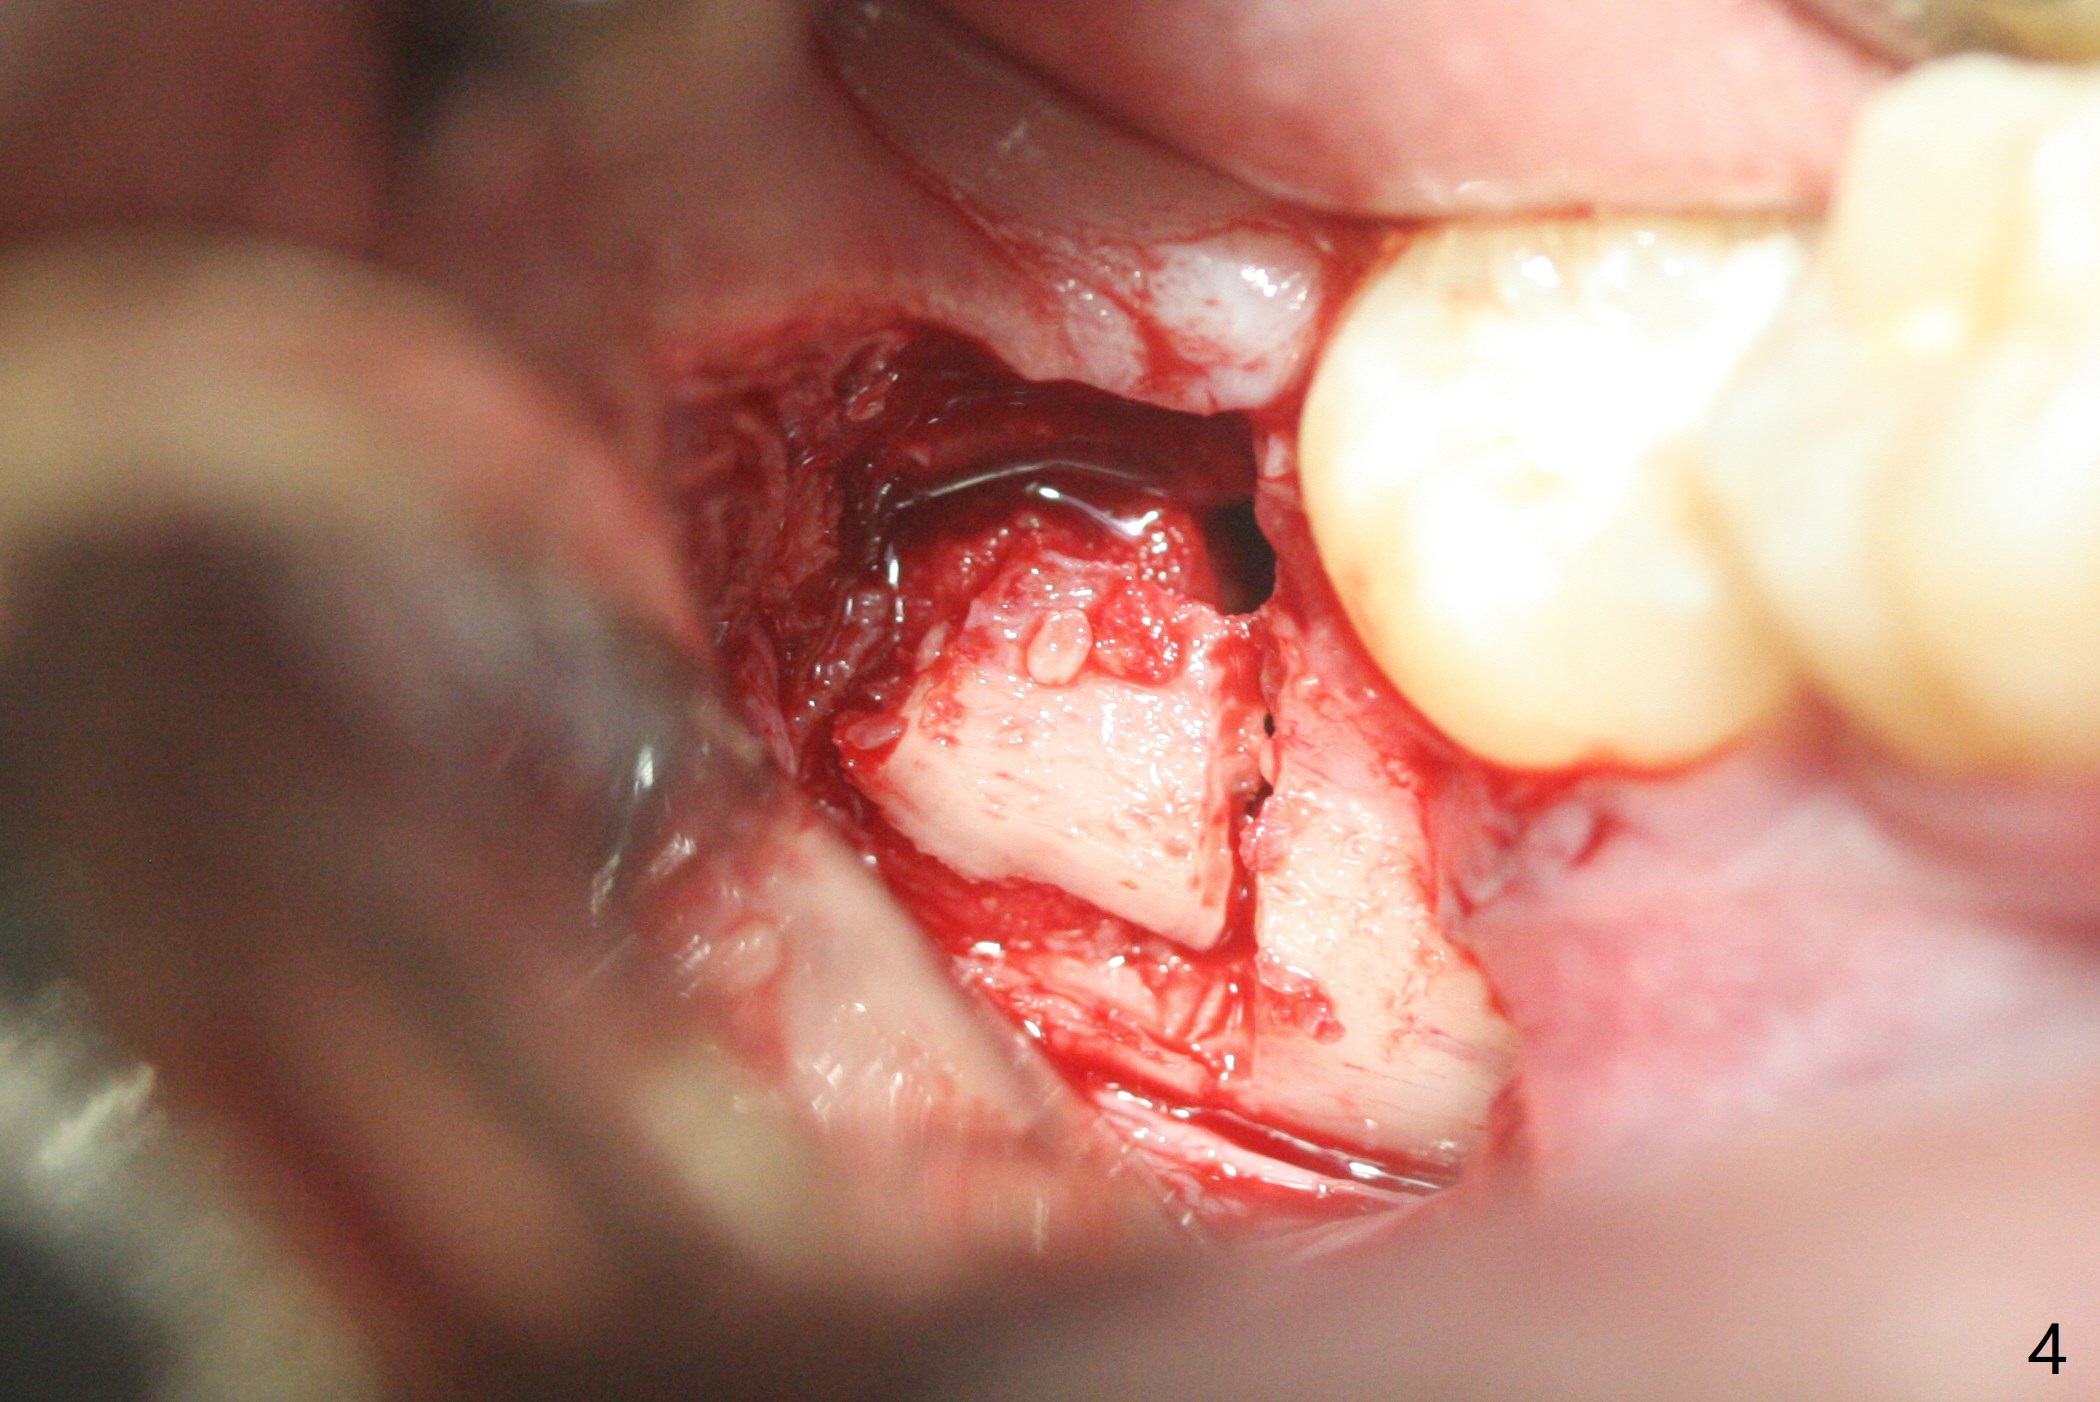

13岁男在矫正医生诊所矫正三年(上中切牙牙根短,图一),转来拔除下颌智齿以助于第二磨牙upright。左侧先拔除,切除三个小块颊侧骨板,保留其中一个与异体骨一起植入牙槽窝近中部分。右侧拔除时,索性切除一个大块颊侧骨板(图二),智齿拔除后,近中牙槽窝放置异体骨(皮质,图三,五:*),远中胶原塞(C),放回颊侧骨板(图四)。Return to Plug Xin Wei, DDS, PhD, MS 1st edition 11/03/2020, last revision 11/03/2020